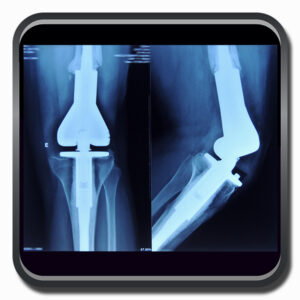

Algumas Cirurgias Complexas realizadas por profissionais da COFIB: